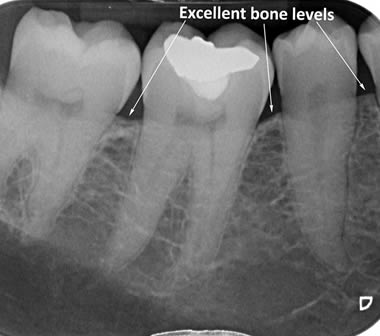

The diagrams below show the different stages of gum disease